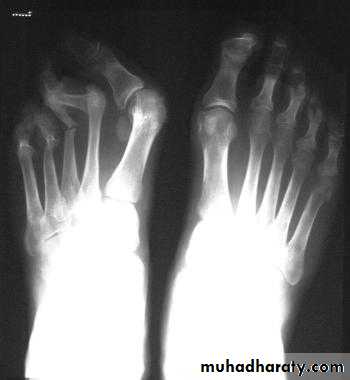

In chronic or recurrent disease, X-rays show joint space narrowing and proliferative erosions.Another characteristic feature is periostitis, especially of metatarsals, phalanges and pelvis, and large, ‘fluffy’ calcaneal spurs.

In contrast to AS, radiographic sacroiliitis is often asymmetrical and sometimes unilateral, and syndesmophytes are predominantly coarse and asymmetrical, often extending beyond the contours of the annulus (‘nonmarginal’)

X-ray changes in the peripheral joints and spine are identical to those in psoriatic arthritis.